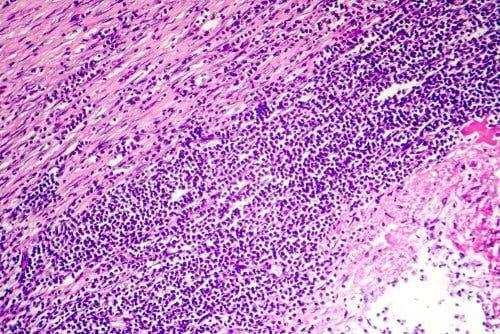

80 %:ssa tapauksia sydänpussitulehduksen syytä on mahdotonta selvittää. Se on kuitenkin hyvin tavallisesti peräisin jonkintyyppisestä infektiosta, hyvin todennäköisesti virusinfektiosta. Joissakin tapauksissa syynä voi olla bakteeri-infektio, mutta vähemmässä määrin, ja vain hyvin harvoissa tapauksissa sydänpussitulehdus voi johtua sieni-infektiosta.